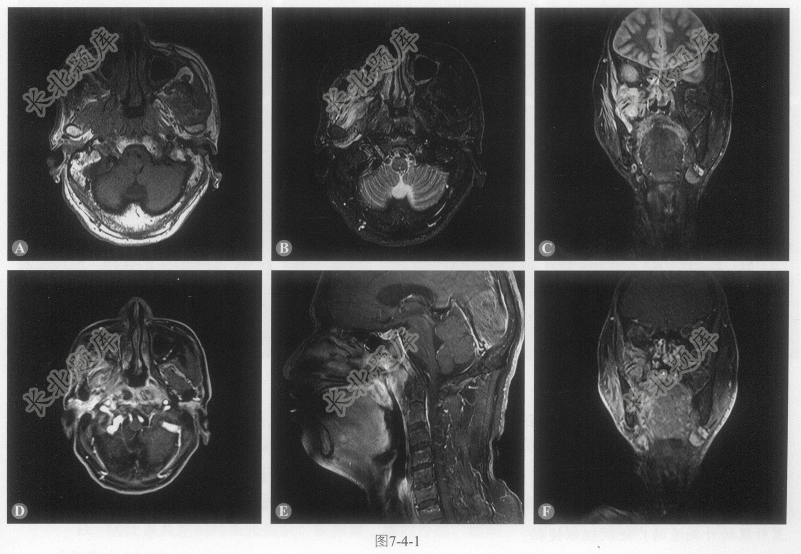

- [材料题] 患者男性,60岁,鼻阻伴回涕带血半年,查体:鼻咽部见新生物膨隆,触之不易出血。右侧额纹、鼻唇沟较对侧变浅。MRI图像如图7-4-1。

A、病灶位于鼻咽部,双侧咽隐窝、咽鼓管咽口变窄、消失

B、病灶T

WI等信号、T2WI脂肪抑制序列呈稍高信号C、增强后病灶明显强化

D、双侧头长肌、右侧翼内外肌、颞下窝及软腭右侧缘受累

E、斜坡、右侧咽旁间隙受侵